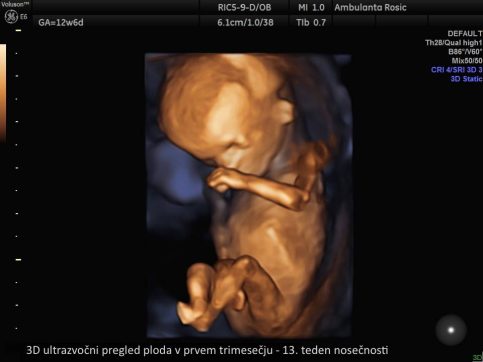

V prvem trimesečju lahko 3D/4D ultrazvočni pregled ploda opravimo ob prvem pregledu ali hkrati z meritvijo nuhalne svetline. Pri 3D/4D ultrazvoku v drugem in tretjem trimesečju nosečnosti določimo tudi lego ploda, položaj posteljice, količino plodovnice, preverimo rast in telesno težo ploda, izmerimo pa lahko tudi pretoke skozi popkovnične žile z Dopplersko ultrazvočno preiskavo za oceno stanja ploda. 3D/4D ultrazvok ploda lahko opravimo tudi ob morfologiji ploda.

3D/4D ultrazvok v nosečnosti izvajamo z vaginalnim (nožničnim) ali abdominalnim (trebušnim) tipalom. Vaginalno tipalo uporabljamo pri ultrazvočni preiskavi v prvem trimesečju, abdominalno tipalo pa v drugem in tretjem trimesečju nosečnosti. S tem imate pri nas nosečnice možnost opraviti 3D/4D ultrazvok ploda že od prvega pregleda v nosečnosti dalje.